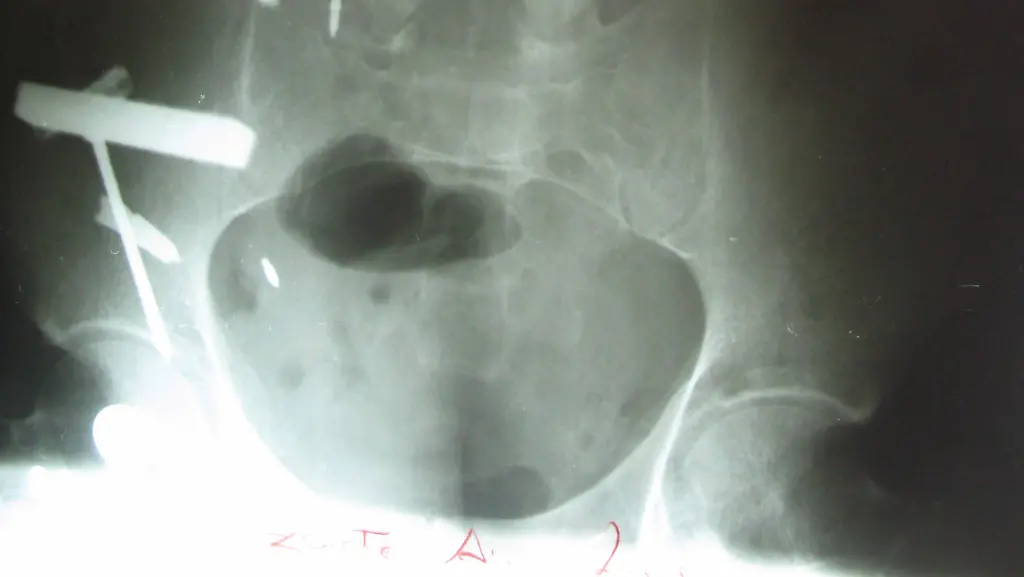

2008 wird ein 38-jähriger Peruaner in die Klinik eingeliefert, der ebenfalls mehrere Metallgegenstände geschluckt hatte. (Foto: REUTERS)

Ärzte in Äthiopien haben mehr als 120 Nägel und andere scharfe Gegenstände aus dem Magen eines Patienten operiert. Insgesamt hätten sie 122 zehn Zentimeter lange Nägel, vier Reißzwecken, zwei Nadeln, einen Zahnstocher und mehrere Glasscherben herausgeholt, sagte der Chirurg Dawit Teare vom St. Paul's Hospital in Addis Abeba.

Der 33-Jährige sei seit zehn Jahren geisteskrank und habe vor zwei Jahren seine Medikamente abgesetzt, erklärte Teare. Vermutlich sei dies der Grund, warum er all diese spitzen und gefährlichen Dinge geschluckt habe - wahrscheinlich mit Hilfe von viel Wasser. Der Mann ist kein Einzelfall. Bereits 2008 wurde ein 38-jähriger Peruaner in die Klinik in Trujillo eingeliefert, weil er ebenfalls mehrere Metallgegenstände geschluckt hatte. Auch er galt als psychisch krank.

Sein Patient habe Glück gehabt, dass sein Magen intakt geblieben sei, sagte der Arzt des 33-jährigen Äthiopiers. "Er hätte sterben können". Inzwischen sei der Mann wieder wohlauf. Teare habe aber die Angehörigen des Patienten angewiesen, in Zukunft auf seinen Geisteszustand zu achten, um zu verhindern, dass er seine Gesundheit noch einmal aufs Spiel setzt.